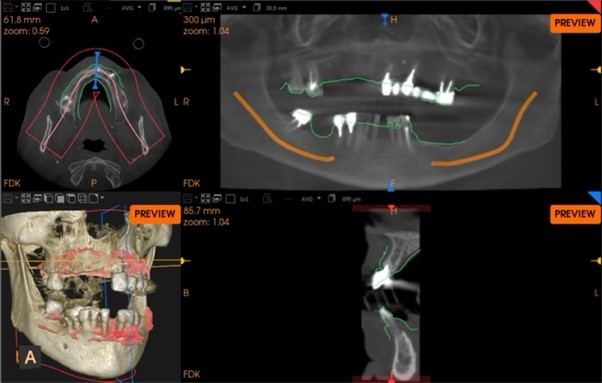

Una paziente di 65 anni si presentava presso la nostra clinica con ampie aree edentule (1° e 3° quadrante), un ponte con mobilità nel 2° quadrante e denti inferiori con scarso supporto parodontale ad eccezione del dente 46 (Fig. 1 a,b,c,d). Dopo un'accurata anamnesi ed esame della CBCT (CS9600®, Carestream Dental, Atlanta, USA) (Fig. 1d), si optava per estrarre le radici e i denti con una prognosi sfavorevole, lasciando 4 molari che credevamo potessero essere conservati (denti 16,17, 26 e 47) al fine di mantenere la dimensione verticale di occlusione (DVO) originale. Si progettava il posizionamento di 12 impianti: 6 impianti nella mascella e 6 nell'arcata inferiore.

Situazione pre operatoria 3

Fig. 1(c)

Situazione pre operatoria 4

Fig. 1(d) Situazione pre-operatoria.